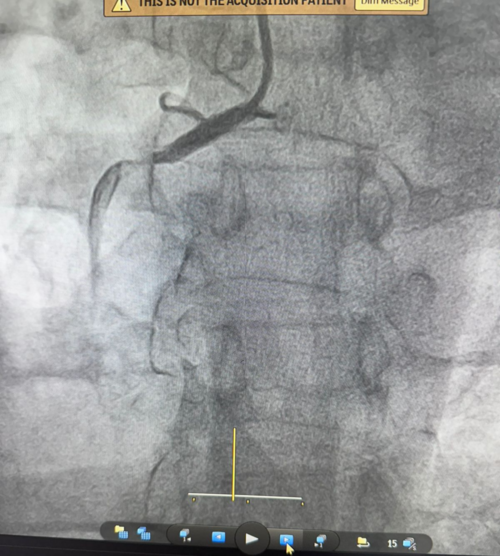

Rapid Life-Saving Primary Angioplasty Case | Dr. Yogesh Jamage

Dr. Yogesh Jamage, leading Consultant Interventional Cardiologist in Miraj–Sangli, successfully managed a high-risk cardiac emergency by perform...

A 28 year male patient diagnosed as hyperacute myocardial infarction (AWMI) referred from periphery for the further management.  Primary angiopla...